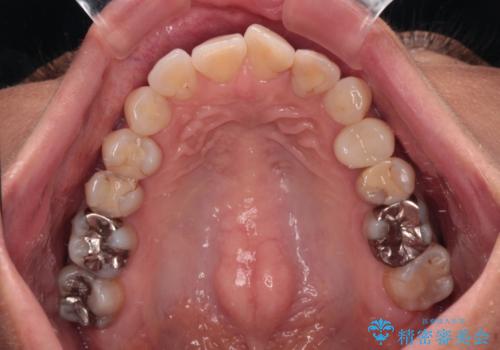

- 目立つ銀歯やむし歯、前歯のデコボコを気にして来院された患者様です。

デコボコはある程度改善できれば良いとのことでしたので、インビザラインの廉価版を用いて矯正治療を行うこととしました。

むし歯治療は、症状のある歯を矯正治療前に処置し、概ね歯列が整ったところで残りのは全て処置し、最後にインビザラインで歯列を仕上げることで、無駄なく治療を進めて行くこととしました。